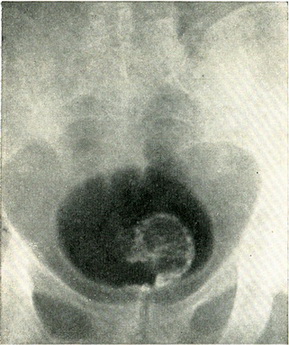

Гістологічне дослідження шматочка пухлини, взятого гострою ложечкою через цистоскоп, дозволяє диференціювати пухлину із грануляційною тканиною, туберкульозом або іншими запальними процесами. За даними біопсії далеко не завжди вдається встановити доброякісність або злоякісність пухлини. При цистографії з 10% розчином сергозина на місці пухлини видно дефект наповнення. Якщо контури міхура залишаються при цьому незмінними, то пухлина з великою ймовірністю можна вважати неинфильтрирующей (рис. 111). Якщо поряд з дефектом наповнення нерівні контури міхура, є асиметрія менаду правою і лівою половиною міхура, то в инфильтрирующем характер пухлини можна не сумніватися (рис. 112).

![]() Рис. 112. Інфільтруючим пухлина сечового міхура. Дефект наповнення праворуч знизу з порушенням контуру міхура. Цистограмма з 10% сергозином. |